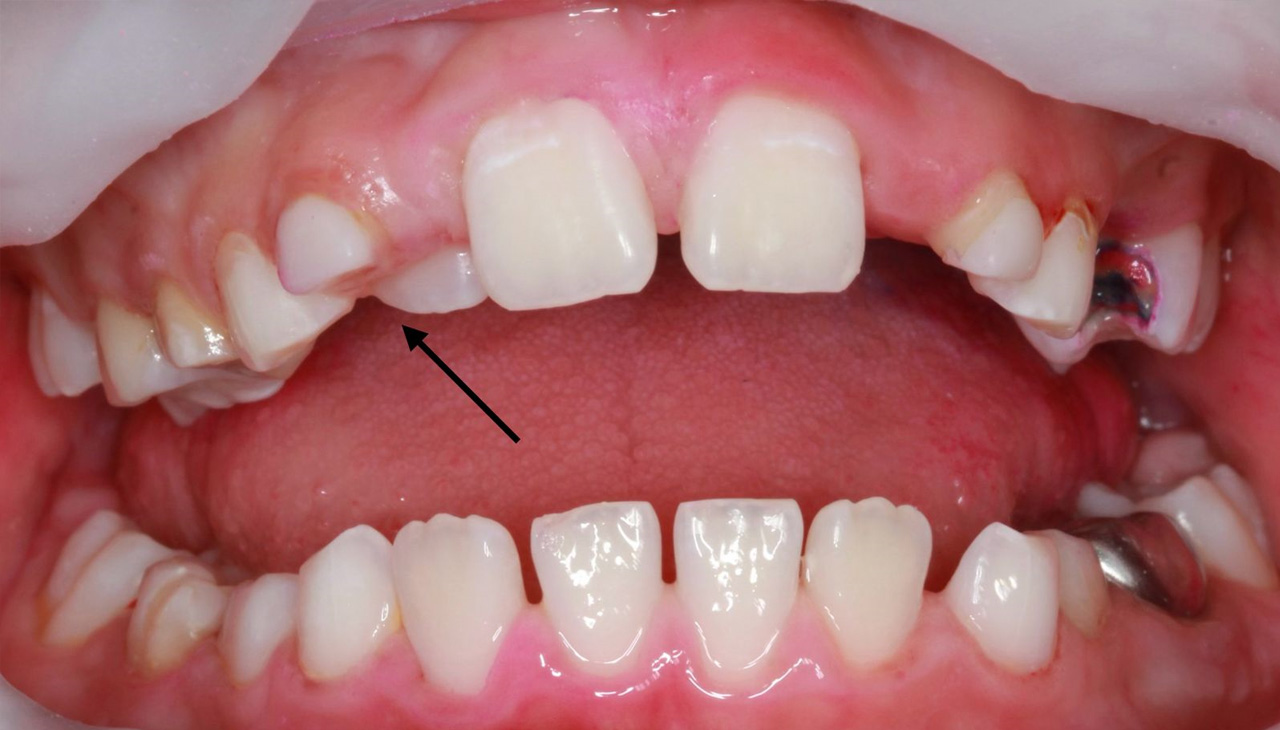

Молочный еще не выпал, а постоянный уже прорезался? Давайте разбираться! (Фото 1)

Что будет, если ничего не предпринимать, в ситуации, когда зубы прорезались в два ряда?

- Неправильный прикус – из-за деформации зубных рядов.

- Травма мягких тканей губы, щеки или неба.